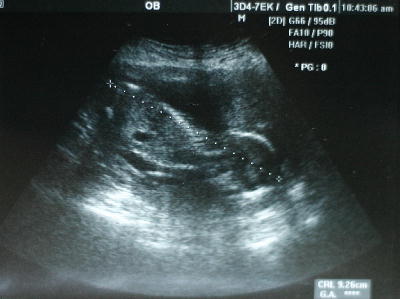

今日はお腹のベビちゃんの4ヶ月の定期検診に行って来ました。

今日で14w4d。今回からお腹の外からのエコーになったので、パパと太郎も

初めてベビちゃんとご対面出来ました。

ベビちゃんの大きさは10cm弱。前回の倍以上に大きくなっていました。